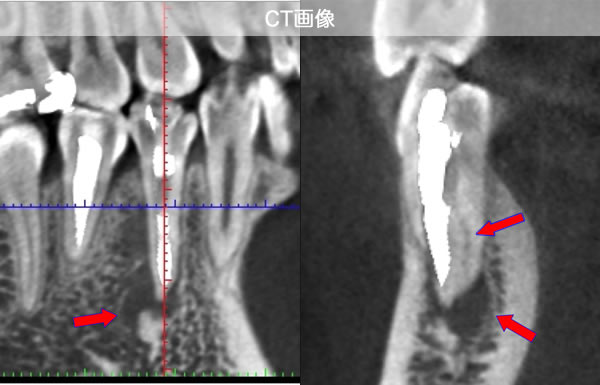

CT画像を見ると根管が2本あることが分かりました。(レントゲンだけでは分かりませんでした。)

| 治療説明 | 右下第2小臼歯、他院で根管治療した後に頬側根尖部から排膿があます。X線CT画像では、根管が2本あり、そのうち舌側が根管充填されていませんでした。顕微鏡下で2根管とも根管充填処置を行い、4ヶ月で、X線透過像は消失しました。 |